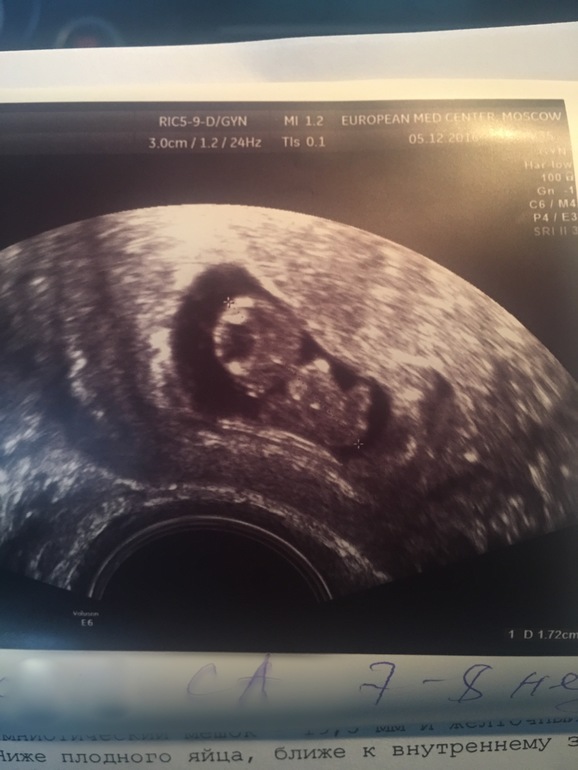

И у меня человек размером с ежевику живет!

У него есть голова, живот, руки и ноги! Впервые такое вижу

1,7мм ктр)

Вы гляньте на него!

Еще у него на месте мозга - вода) ну вон жидкость, видите) долго смеялась на этот счет, что весь в мать) это норма сейчас, я шучу конечно.